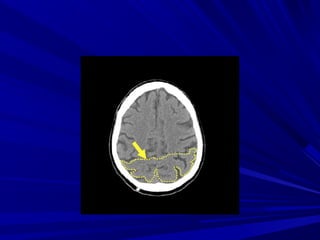

occipital infarctionoccipital infarction